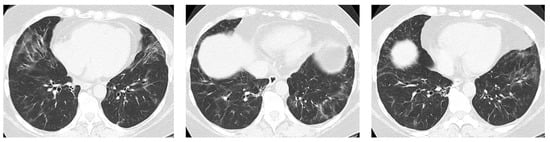

4.1. How Does Radiologic/Histopathologic Pattern Influence the Clinical Picture and Management of pSS-ILD Patients? What Is the Role of Lung Biopsy?

- Egashira, R.; Kondo, T.; Hirai, T.; Kamochi, N.; Yakushiji, M.; Yamasaki, F.; Irie, H. CT Findings of Thoracic Manifestations of Primary Sjögren Syndrome: Radiologic-Pathologic Correlation. Radiographics 2013, 33, 1933–1949. [Google Scholar] [CrossRef] [PubMed]

- Flament, T.; Bigot, A.; Chaigne, B.; Henique, H.; Diot, E.; Marchand-Adam, S. Pulmonary manifestations of Sjögren’s syndrome. Eur. Respir. Rev. 2016, 25, 110–123. [Google Scholar] [CrossRef]

- Dong, X.; Zhou, J.; Guo, X.; Li, Y.; Xu, Y.; Fu, Q.; Lu, Y.; Zheng, Y. A retrospective analysis of distinguishing features of chest HRCT and clinical manifestation in primary Sjögren’s syndrome-related interstitial lung disease in a Chinese population. Clin. Rheumatol. 2018, 37, 2981–2988. [Google Scholar] [CrossRef]

- Dong, X.; Gao, Y.-L.; Lu, Y.; Zheng, Y. Characteristics of primary Sjögren’s syndrome related lymphocytic interstitial pneumonia. Clin. Rheumatol. 2021, 40, 601–612. [Google Scholar] [CrossRef] [PubMed]

- Ito, I.; Nagai, S.; Kitaichi, M.; Nicholson, A.G.; Johkoh, T.; Noma, S.; Kim, D.S.; Handa, T.; Izumi, T.; Mishima, M. Pulmonary manifestations of primary Sjogren’s syndrome: A clinical, radiologic, and pathologic study. Am. J. Respir. Crit. Care Med. 2005, 171, 632–638. [Google Scholar] [CrossRef]